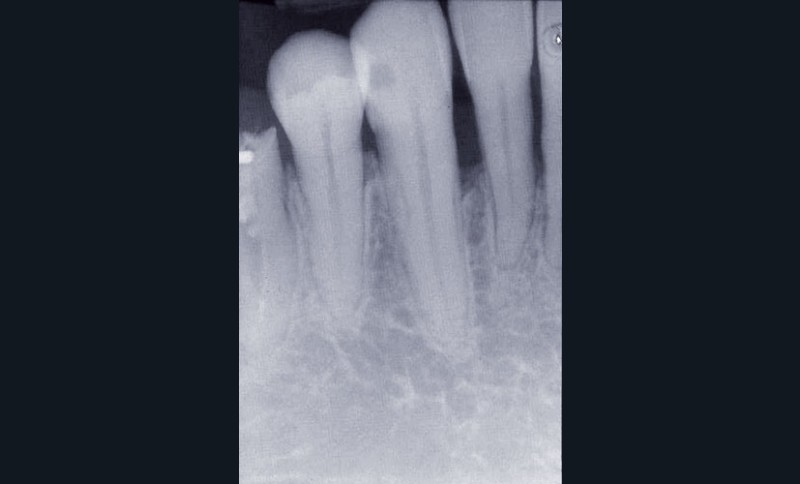

Les examens cliniques et radiographiques montrent une parodontite chronique généralisée (fig. 1a à m).